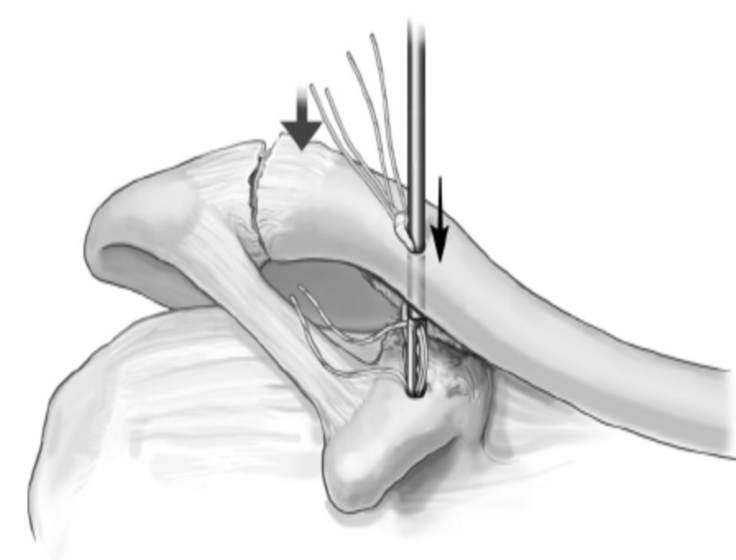

手术方法

1.复位肩锁关节,1枚克氏针临时固定关节。

2.导针定位,在锁骨远端内侧3cm处自背侧向喙突基底部用4.5mm空心钻头钻孔。

(在锁骨远端钻孔时,钻孔位于锁骨前中1/3处,这样垂直进针才会打入喙突基底正中。)

3.假体准备,在钮扣钢板的外侧和内侧两孔依次穿入2根5号爱惜邦线,袢上穿入1根缝线留作牵引。(测量喙锁间距,选择袢长度要略大于测量值的带袢endobutton钢板。)

4.将钮扣钢板与缝线推至喙突下,将缝线袢向上拉出锁骨表面,在袢下方放入第2块钮扣钢板系紧外侧缝线固定。(注意:放置第二个endobutton时袢的方向要与钢板垂直!还一定要放平以便系缝线!

5.沿锁骨上钻孔的前外侧约1cm处另钻一孔,将内侧缝线打结在该孔上重建斜方韧带。这样就把喙锁韧带重建了。

6.拔出临时克氏针,清洗伤口并缝合。